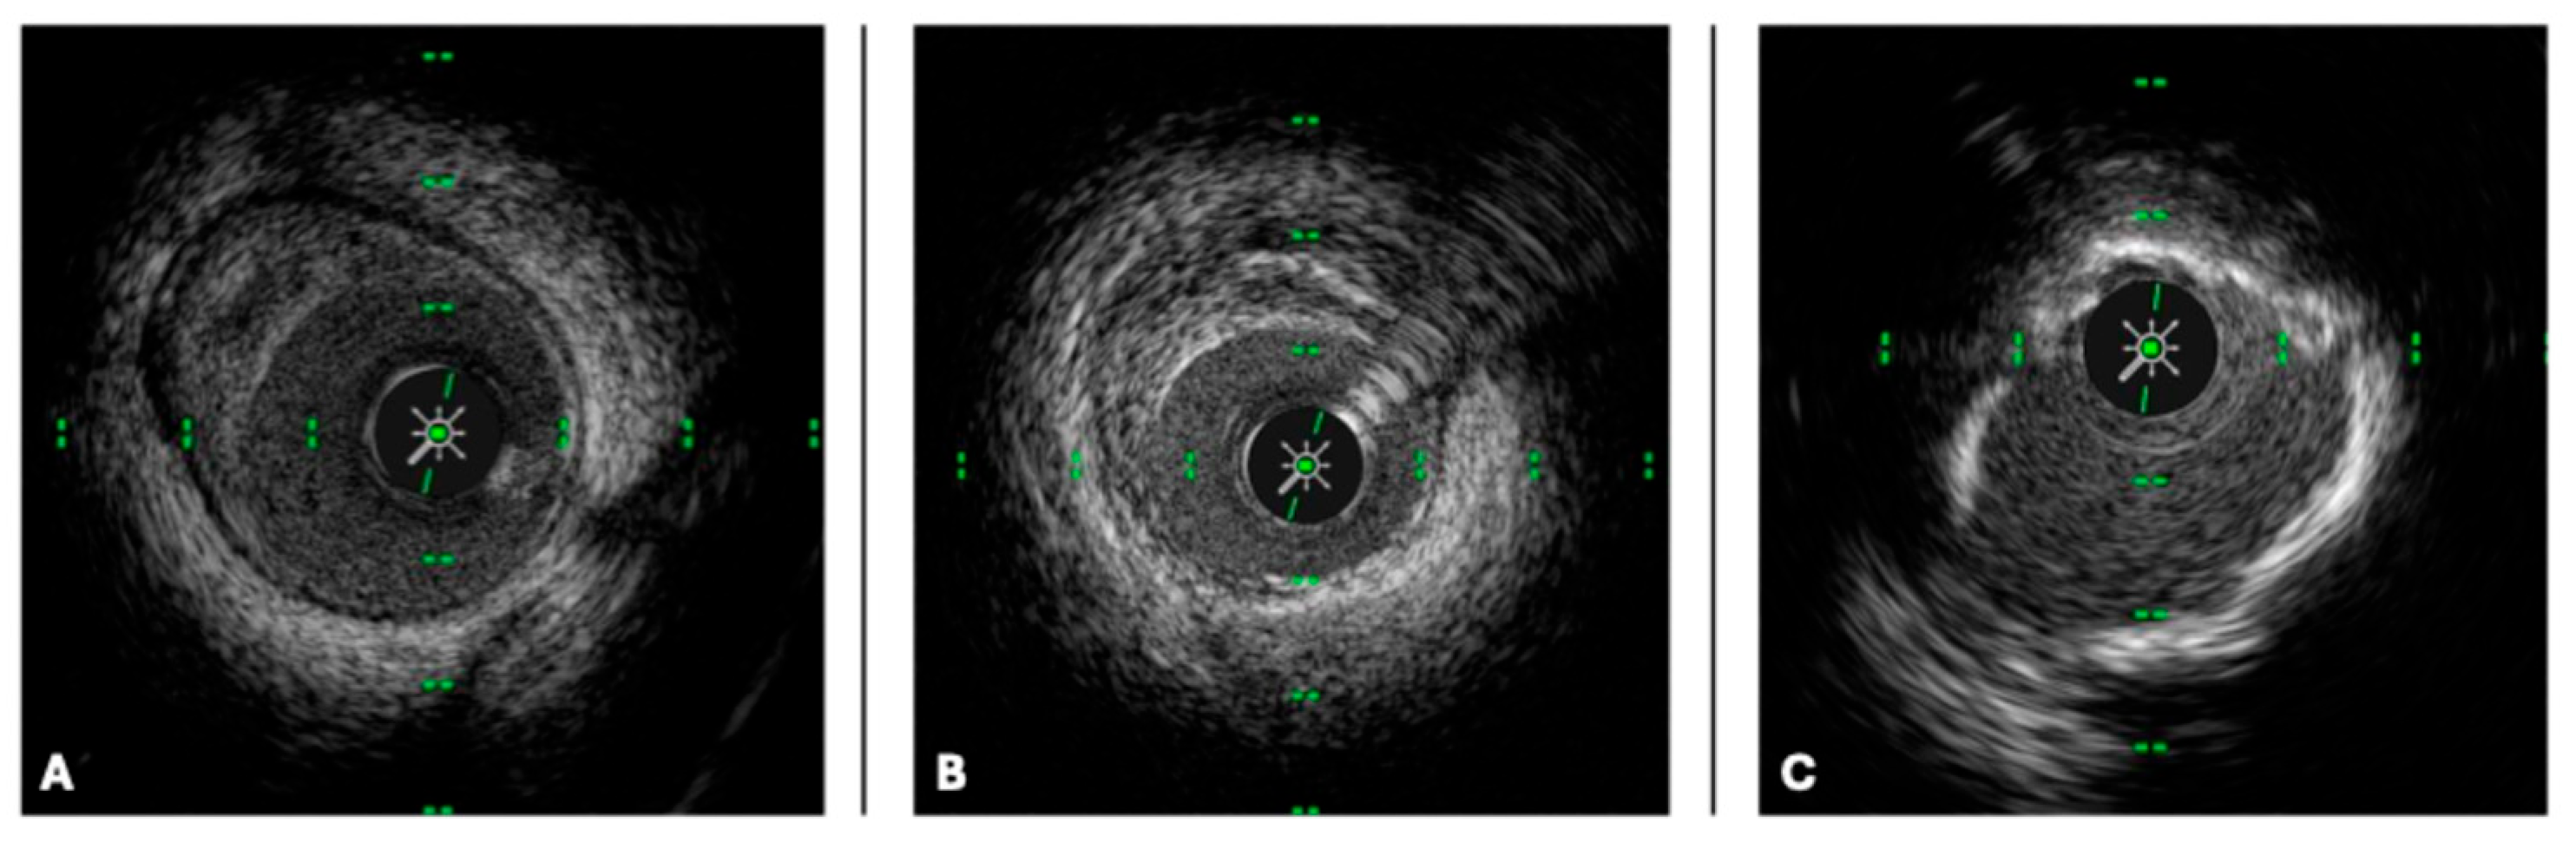

2.1. IVUS Technology